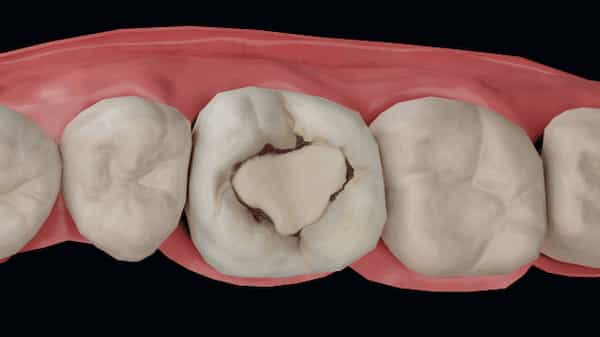

پوسیدگی سطح جونده

پوسیدگی سطح جونده معمولا روی دندانهای آسیاب دیده میشود؛ همان دندانهایی که مسئول خرد کردن و جویدن غذا هستند. سطح این دندانها دارای شیارها و فرورفتگیهای طبیعی است که بهراحتی محل تجمع ذرات غذا و باکتریها میشود.

در بسیاری از افراد، حتی با مسواک زدن منظم، این شیارها بهطور کامل تمیز نمیشوند. به همین دلیل پوسیدگی سطح جونده یکی از شایعترین انواع پوسیدگی دندان، بهخصوص در کودکان و نوجوانان است. در مراحل اولیه ممکن است فقط تغییر رنگ یا لکههای تیره روی سطح دندان دیده شود.

اگر این نوع پوسیدگی بهموقع درمان نشود، میتواند به عمق دندان نفوذ کند و به عاج برسد. در این مرحله حساسیت به سرما و گرما یا درد هنگام جویدن غذا بروز پیدا میکند و درمان معمولا نیازمند ترمیم یا پرکردگی خواهد بود.